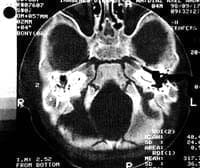

Se trata de un paciente de sexo masculino de 7 meses de edad, producto del primer embarazo de curso normal y parto vaginal normal. Quien presenta sintomatología de 2 meses y medio de evolución consistente en otalgía y otorrea serosanguinolenta derecha por lo cual recibió tratamiento médico, sin obtener resolución de su sintomatología. En vista de que no hay mejoría de su cuadro clínico se decide hospitalización para manejo con antibioticoterapia. Durante su hospitalización presenta parálisis facial derecha por lo cual se realiza Tomografia Axial Computarizada de hueso temporal, en la que se evidencia imagen de tejidos blandos a nivel de mastoides, antro mastoideo y epitímpano sin comprometer la cadena osicular (Fig. 1, 2, 3). Al examen físico inicial se encontró pequeña masa a nivel del piso del conducto auditivo externo.

| FIGURA 1 | FIGURA 2 | FIGURA 3 |